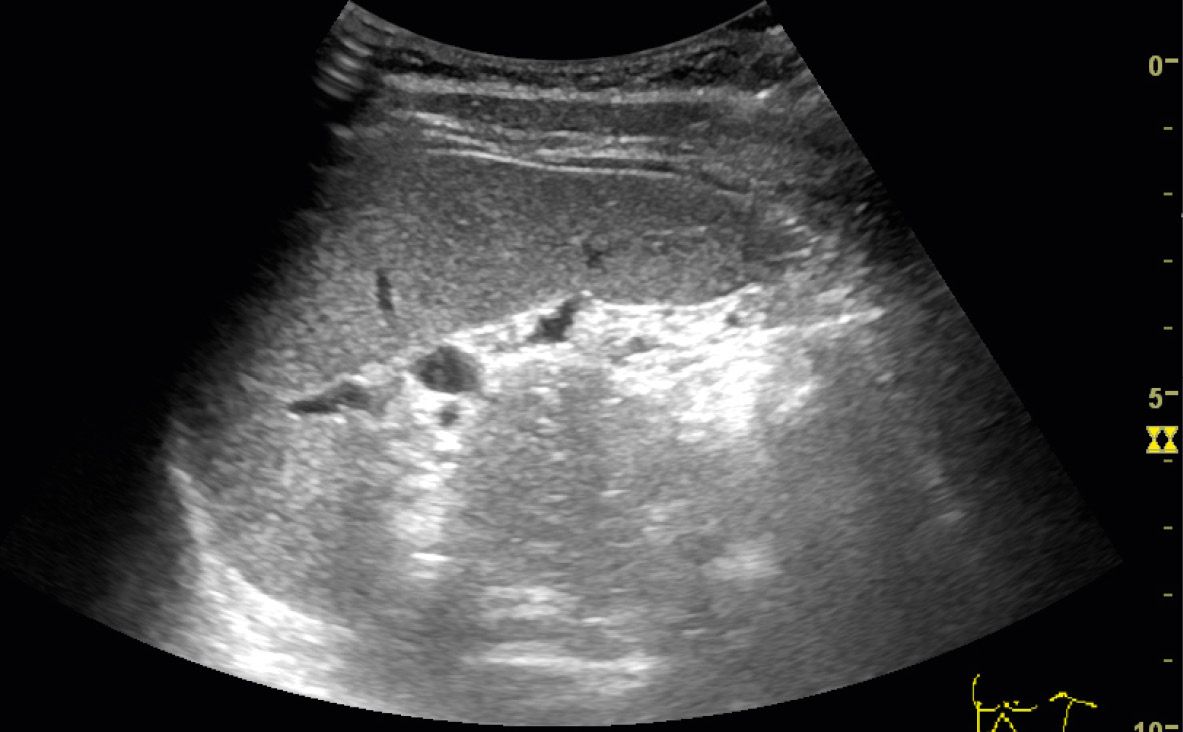

Point of care renal ultrasonography for the busy nephrologist A What Does A Shadow On My Kidney Mean Even a small amount of blood can cause a color change. It is true that a ct will pick up a tumour, but it may also show a shadow if there has been infection present for a while (this may be low level that. The survival rate for kidney cancer drops significantly at advanced stages. Find out about kidney cancer,. What Does A Shadow On My Kidney Mean.

Body Imaging Kidney International Contrast Ultrasound Society What Does A Shadow On My Kidney Mean Find out about kidney cancer, including the. But if symptoms indicate a tumor, the sooner you can get treatment, the better. The same symptoms that suggest kidney cancer can also signal a variety of other conditions. Even a small amount of blood can cause a color change. It is true that a ct will pick up a tumour, but it. What Does A Shadow On My Kidney Mean.

Point of care renal ultrasonography for the busy nephrologist A What Does A Shadow On My Kidney Mean Find out about kidney cancer, including the. Hard, mineralized deposits in tissues, like kidney stones or gallstones, can cause pronounced acoustic. The same symptoms that suggest kidney cancer can also signal a variety of other conditions. It is true that a ct will pick up a tumour, but it may also show a shadow if there has been infection present. What Does A Shadow On My Kidney Mean.

Point of care renal ultrasonography for the busy nephrologist A What Does A Shadow On My Kidney Mean It is true that a ct will pick up a tumour, but it may also show a shadow if there has been infection present for a while (this may be low level that. Hard, mineralized deposits in tissues, like kidney stones or gallstones, can cause pronounced acoustic. The survival rate for kidney cancer drops significantly at advanced stages. But if. What Does A Shadow On My Kidney Mean.